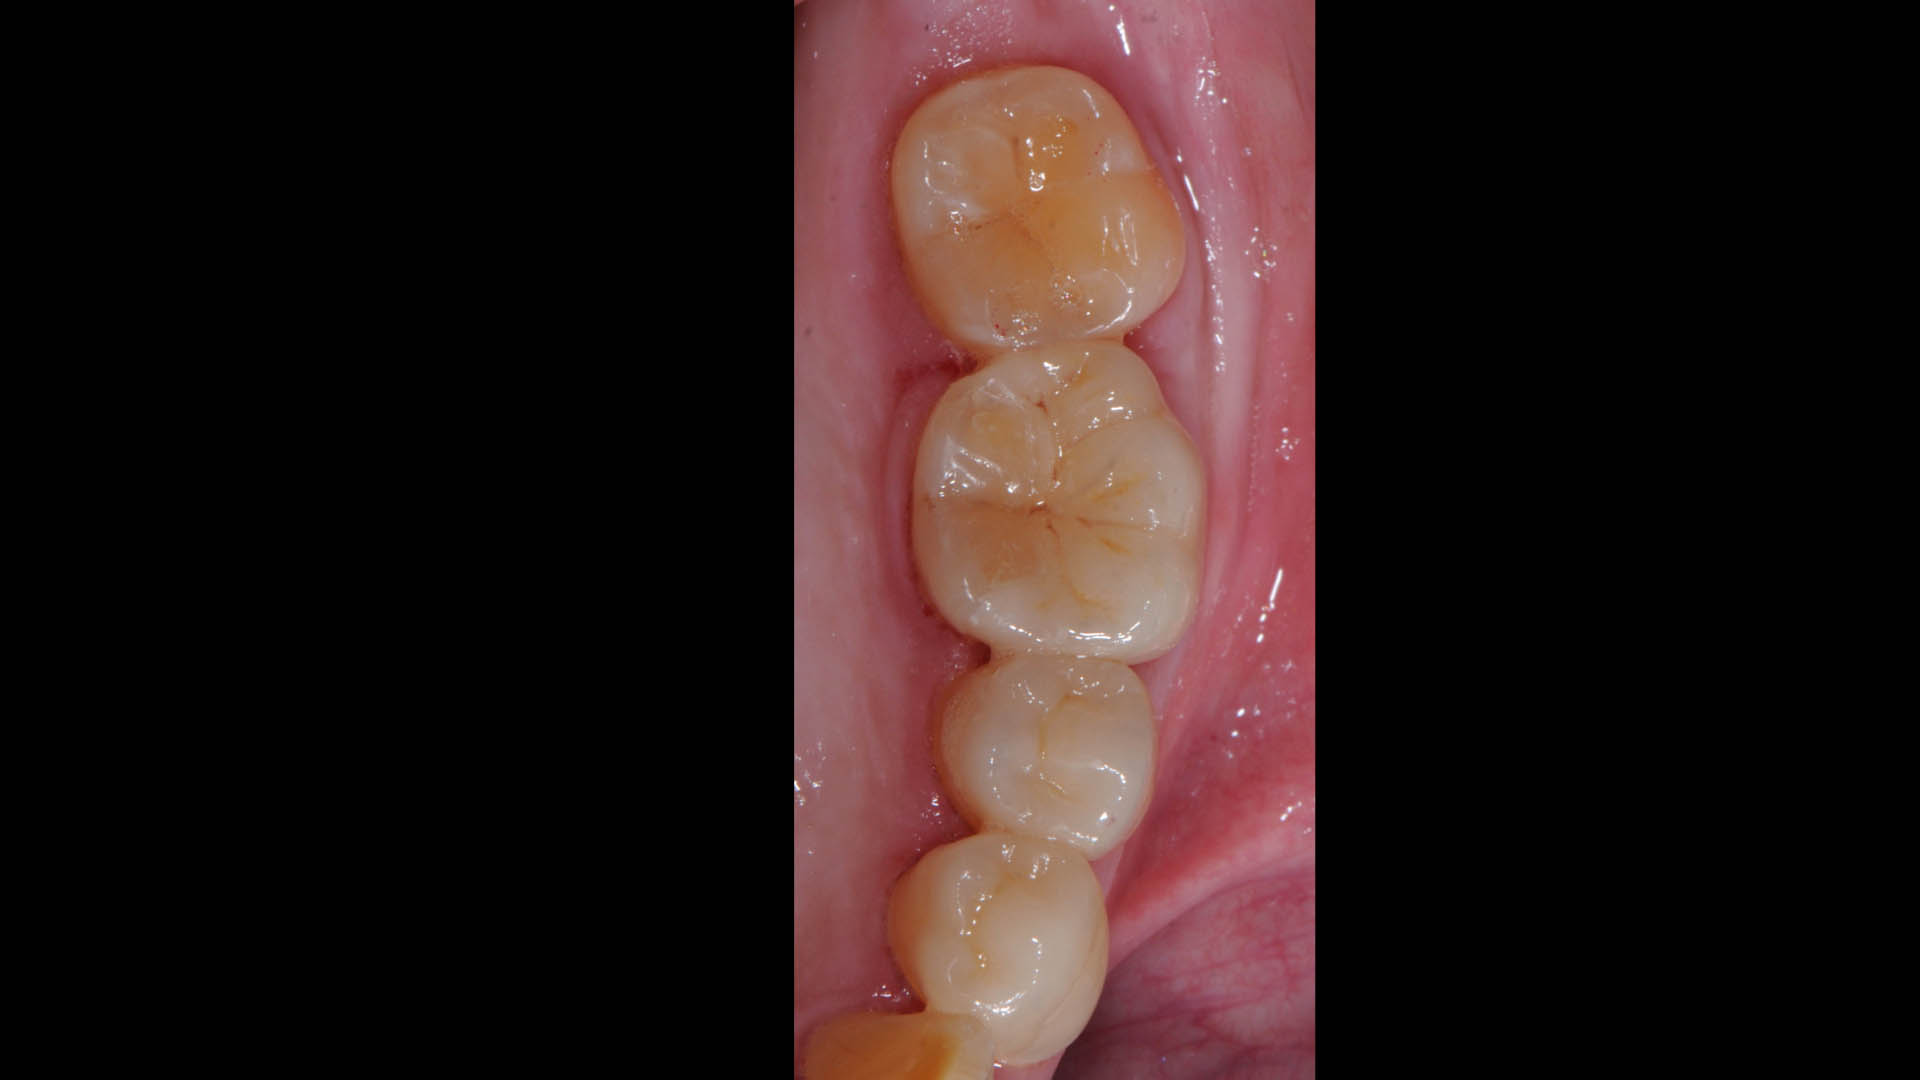

Take a glimpse into the magic of Coral Gables Dentistry through our before and after pictures. See firsthand the incredible smile makeover transformations that have brought confidence and joy to our patients.